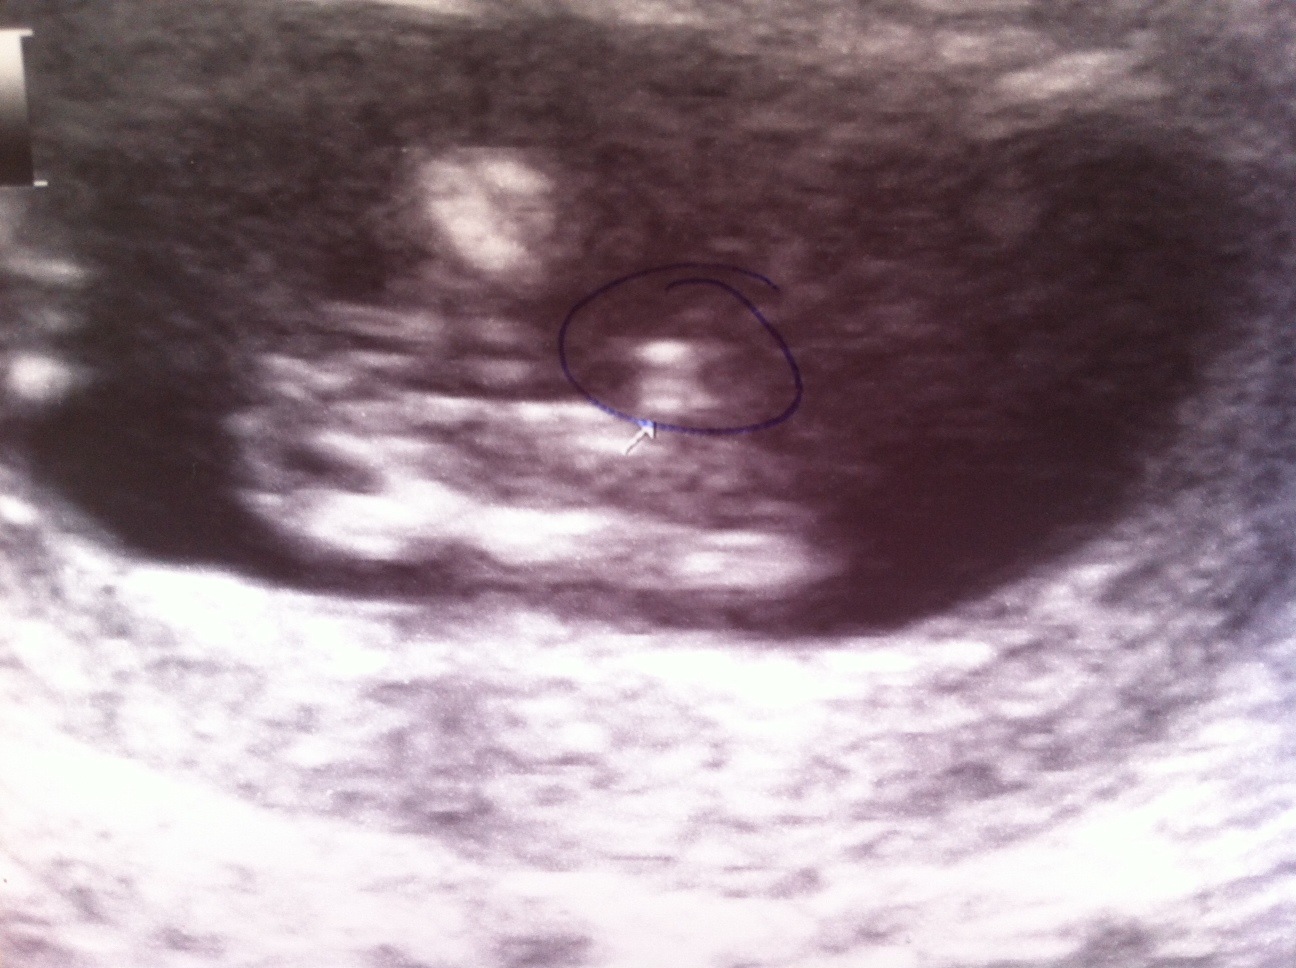

what do you think? its a potty shot with 13 weeks. is it a boy or girl?

Gosh, I wish it were clearer...I guess it looks like a girl? You saw the live version so was there nothing between the legs?

I don't think that you can see the gender by genitals...only NUB at these weeks (sorry slecht Engels maar ik bedoel piemeltje en hamburgertje lijken nu nog veel op elkaar, het is nog in ontwikkeling zeg maar) i'll pray for you that this are HER lips what we see..,😘

According the tech today it is a boy....the tech yesterday thought girl.... See my post of today.

The second thech said it was a cord and not privat parts of the baby she said the other tech didn't see it well....

this picture is not good for gender guessing, we do see some parts OF the gender, but not clear at all, totally 50/50 based on this still shot... xxx

With the 17 weeks 3d scan she confirmed it is a boy.